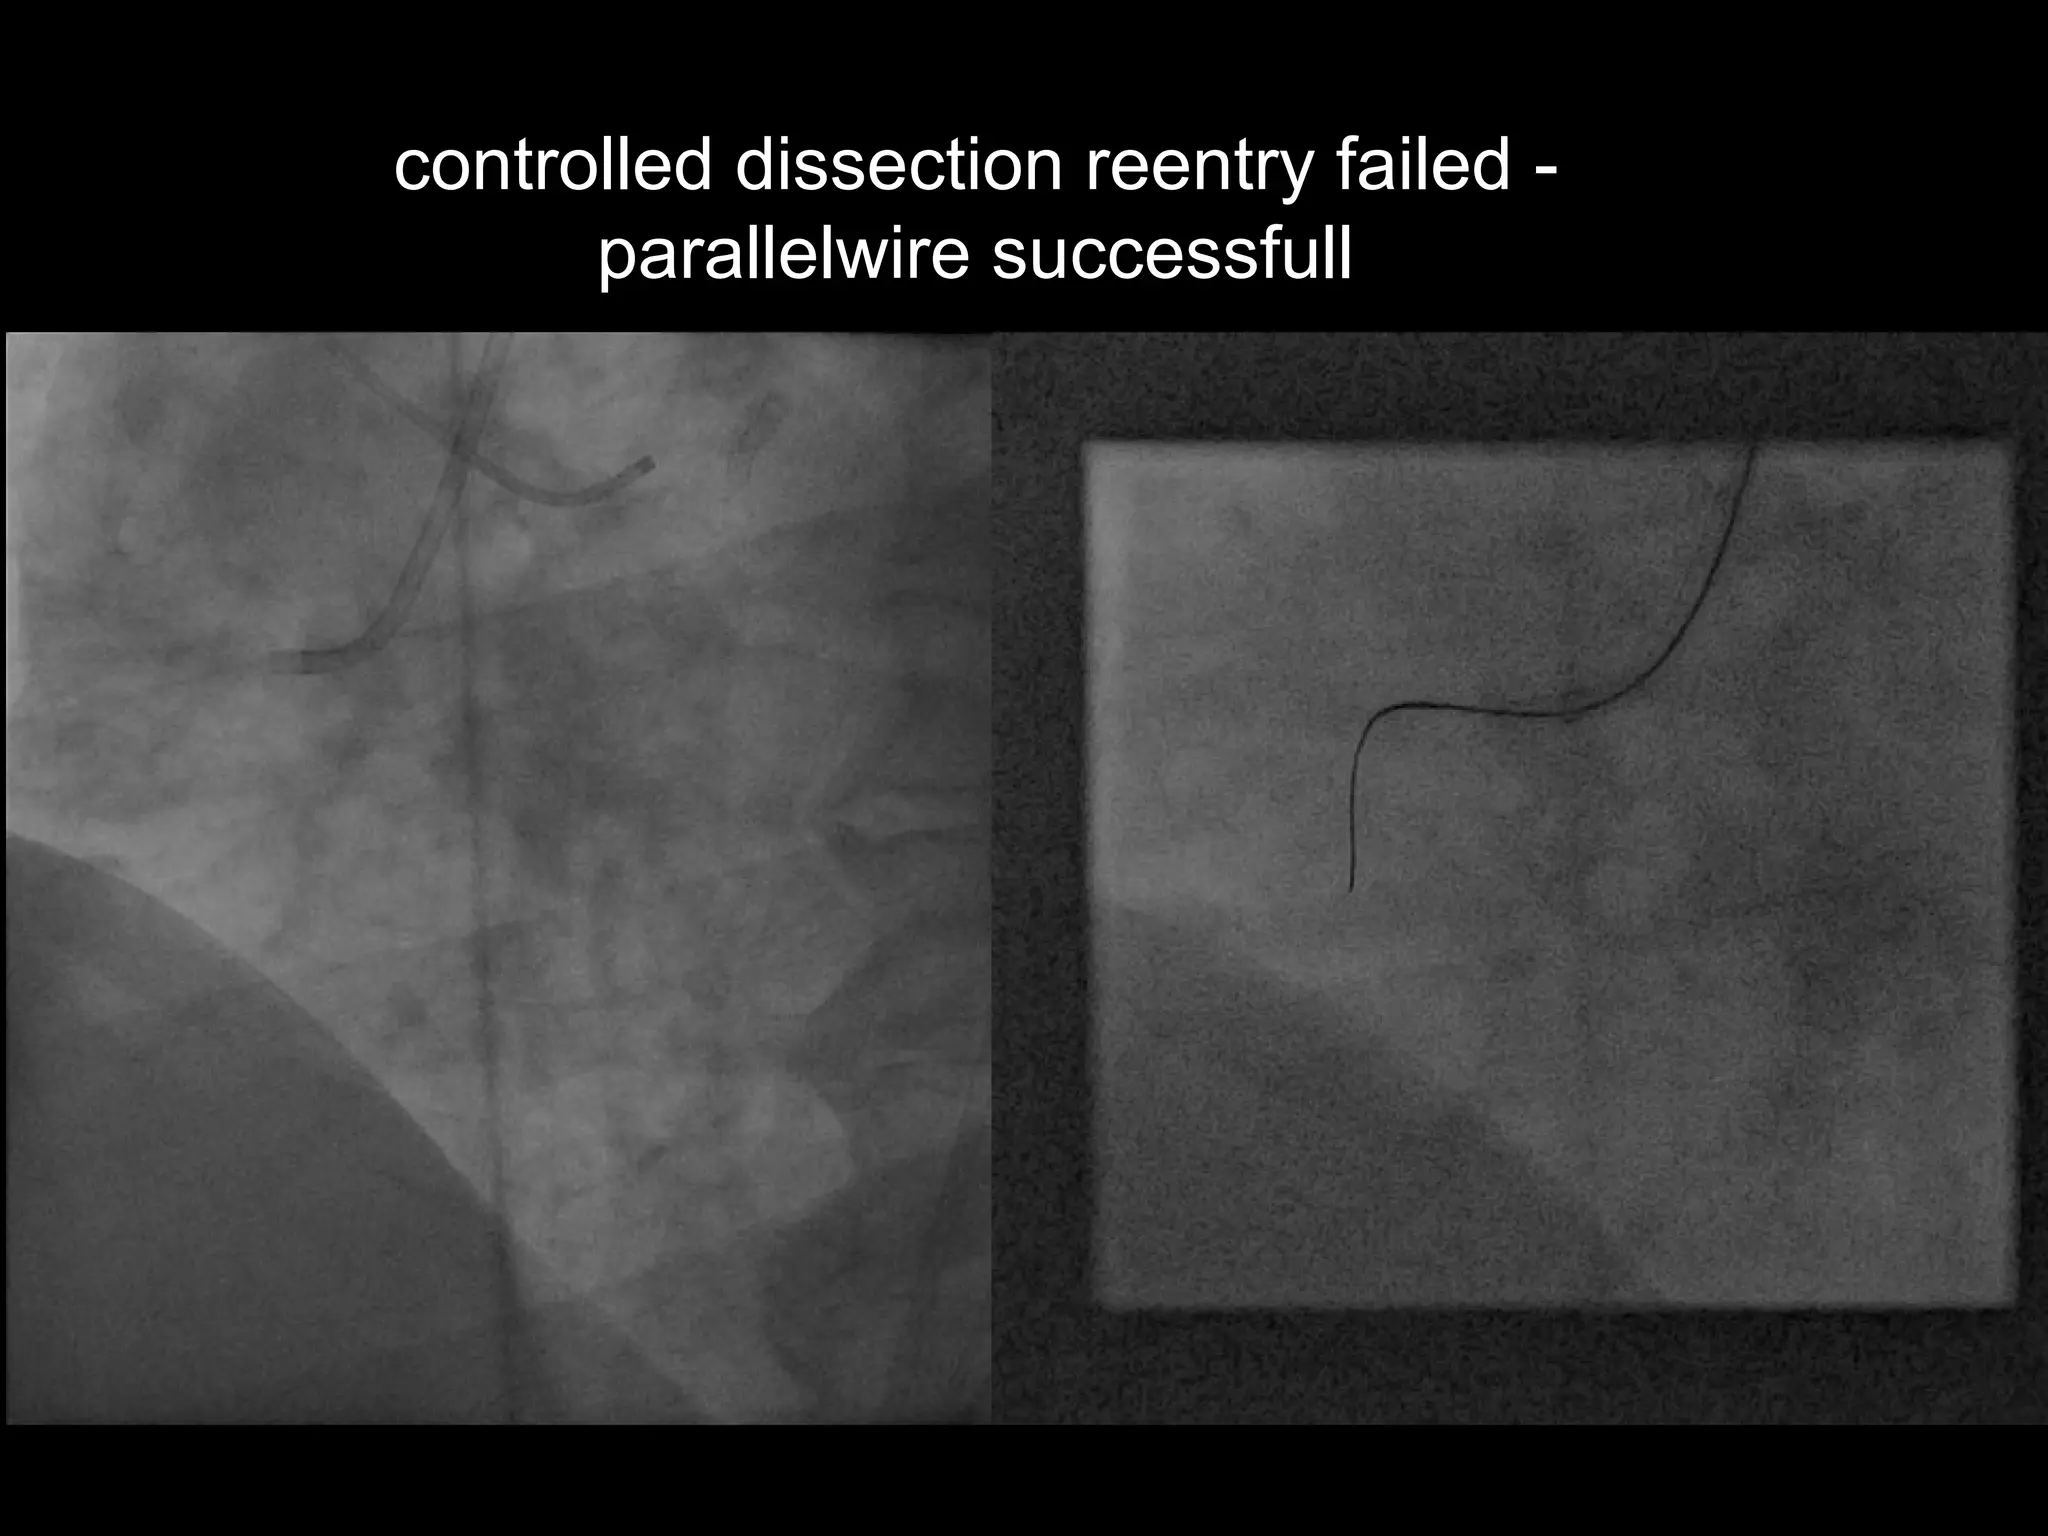

controlled dissection reentry failed -

parallelwire successfull